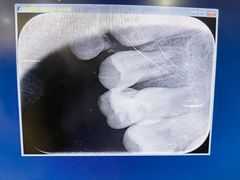

• 泰康拜博口腔(凯迪大厦店)

• -泰康拜博口腔(凯迪大厦店)